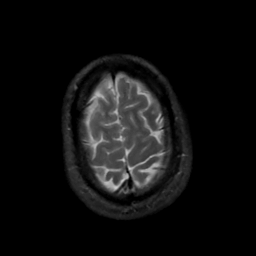

MR Study #5, March 10, 1991 -- Slice #45

[Home][Help][Clinical][Tour 1][Tour 2] Slice 45